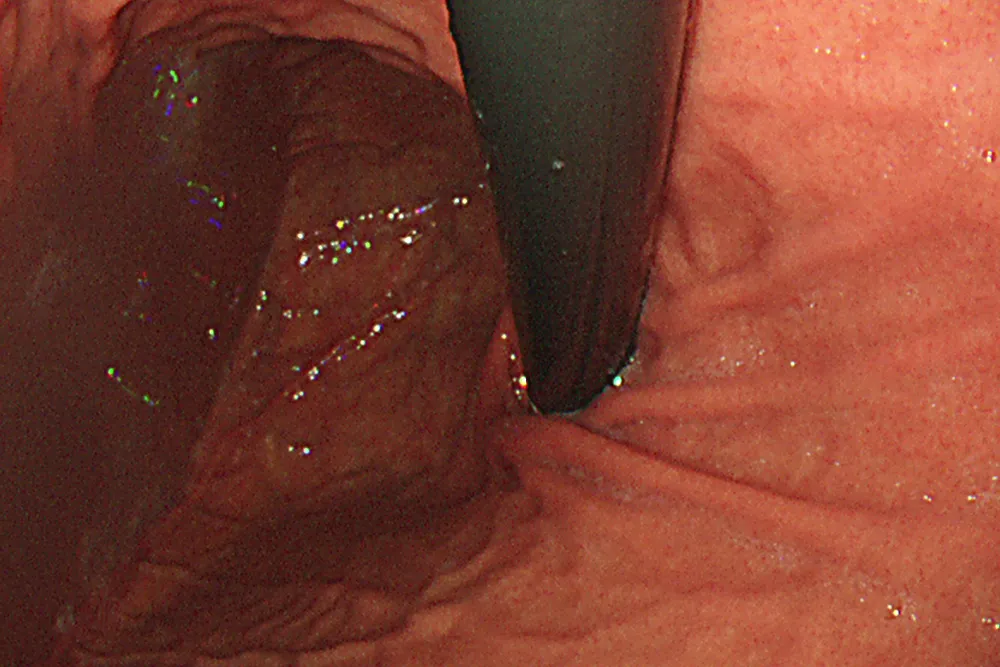

当院で施行する大腸内視鏡検査中に発見された切除可能な大腸ポリープは、その場ですぐ切除します。定期的に大腸カメラ検査を受けて大腸ポリープを全て切除していれば、大腸がんを予防できることがわかっています。

内視鏡AIとは、内視鏡検査時に病変が疑われる領域に対してリアルタイムに検出し、大腸がん・胃がん・食道がんの早期発見をサポートするシステムです。

AI機能のメリットは、検査における取りこぼしを減らせることです。内視鏡施行医の目とAIの目を融合することで見落としを限りなくゼロにするように努力しています。